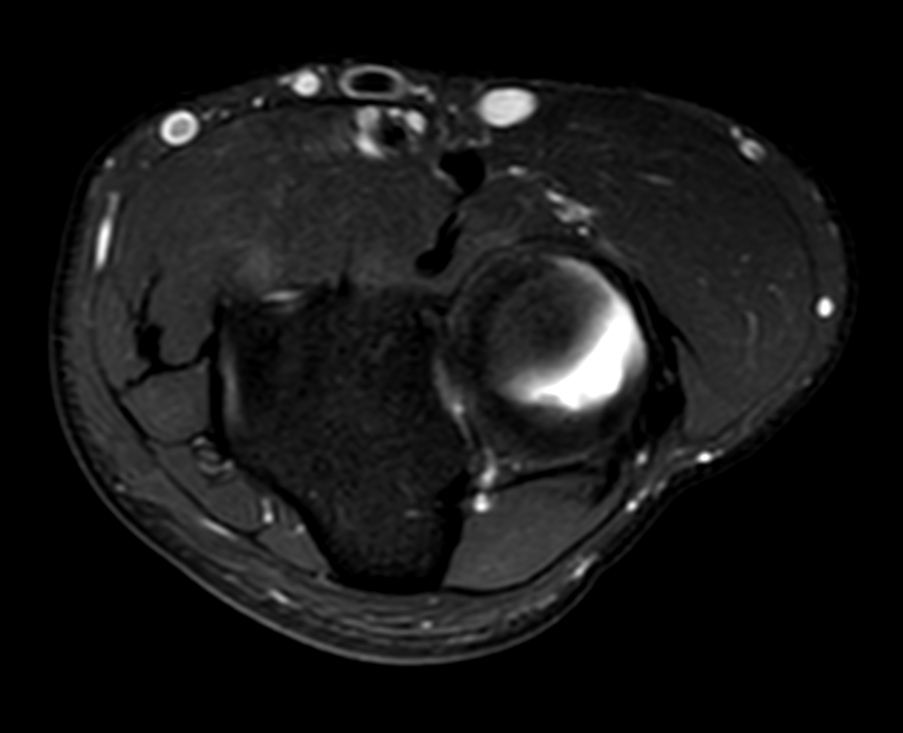

High quality Elbow imaging with Compressed SENSE

Spital Uster, Switzerland